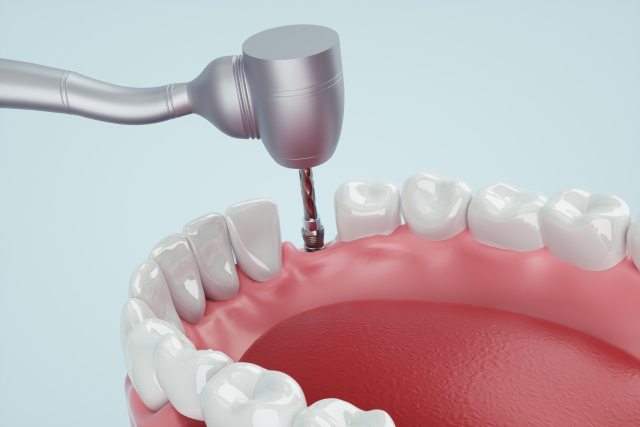

手術の手順

1

奥歯が1本抜けてしまった場合、従来はブリッジや入れ歯で治療していました。

しかし、それでは残っている歯に負担がかかったり、傷つけたりしてしまいます。

-

2

残っている歯の為にインプラント治療を選びました。

まず、歯が抜けてしまったところに、インプラントを植えこむためのスペースをつくります。

3

インプラントを植えこむためのスペースに、もともとあった歯の形に合わせたインプラントを植えこみます。

4

インプラントを植えこんだら、歯肉で蓋をして6~12週間待ちます。

この期間を治癒機関と呼び、この間にインプラントが顎の骨と一体になります。